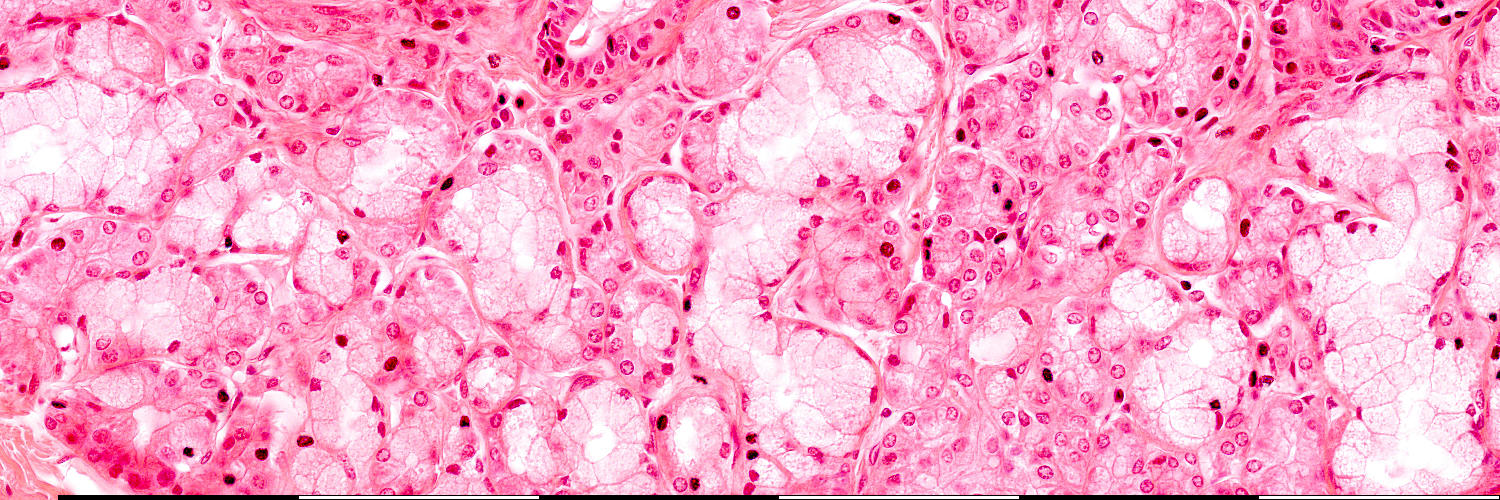

Tongue

Mucous

Serous

Lumen

Nuclei